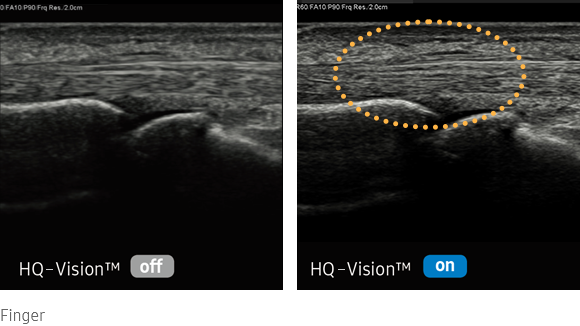

Clarify blurred area to provide clearer images

HQ-Vision provides clearer images by mitigating the characteristics of ultrasound images that are slightly blurred than the actual vision.

medical diagnostics : HQ-Vision™